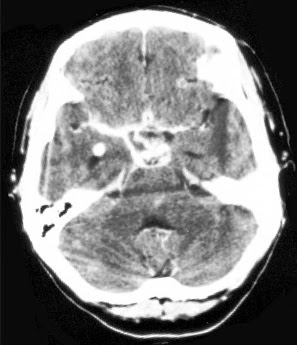

Trên CT, một xuất huyết dưới nhện xuất hiện mật độ cao trong rãnh và bể chứa nước. Các vùng đảo và đáy bể nên được xem xét cẩn thận các dấu hiệu tinh tế của xuất huyết dưới màng nhện. Xuất huyết dưới nhện có thể có liên quan đến xuất huyết não thất và não úng thủy.

Mật độ cao trong máu lấp đầy các bể chứa dịch não tủy (đầu mũi tên) ở bệnh nhân này có xuất huyết từ động mạch não giữa trái .

Lưu ý phình động mạch não giữa (mũi tên).